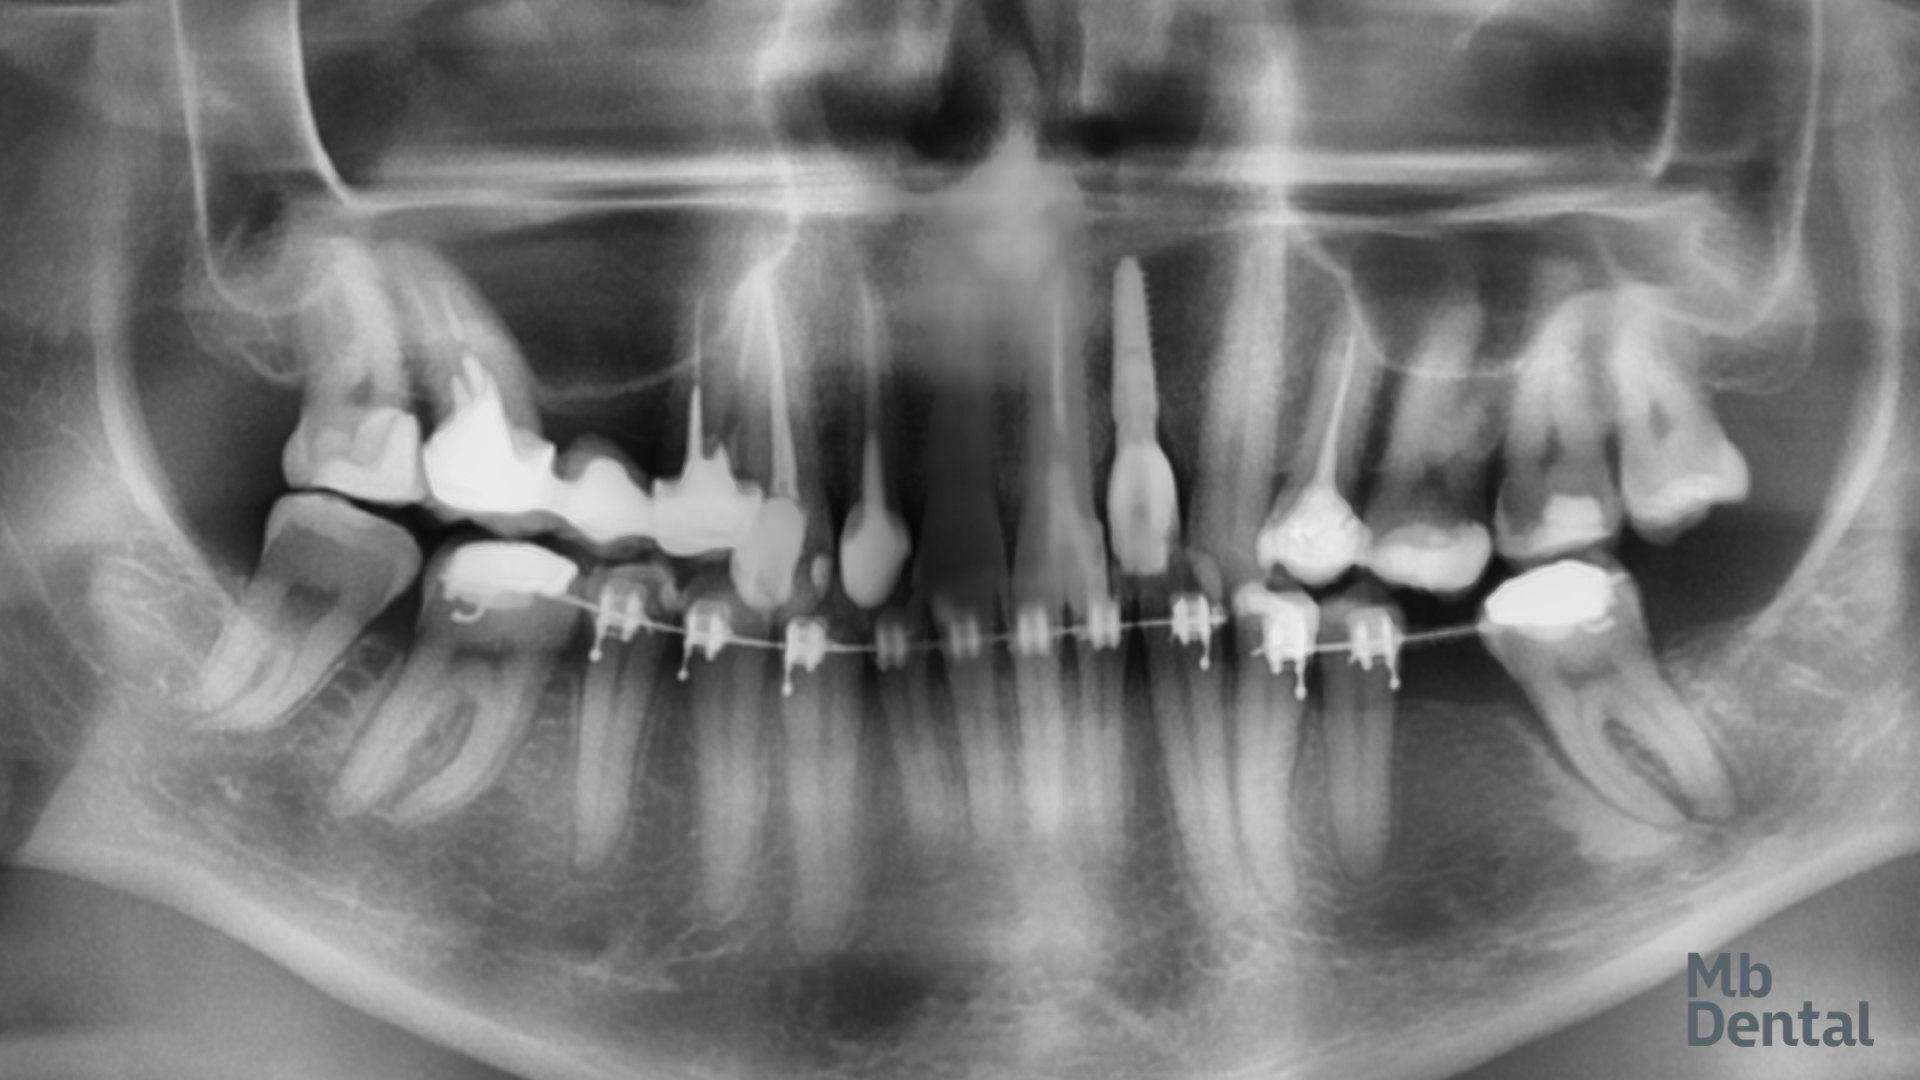

Inițial, la arcada inferioară a fost rezolvată inghesuirea dentara frontala si s-a creat spațiu pentru inserarea unui implant deoarece un molar a fost extras in trecut iar dinții vecini au migrat parțial. La nivelul dintilor superiori a fost necesara extractia unui incisiv lateral tratat endodontic a carei rădăcina s-a fracturat. Acesta a fost de fapt si unul dintre motivele care a motivat pacientul sa solicite o reabilitare complexă.

S-a realizat inserarea unui implant imediat postextractional protezat cu o coroana provizorie. Deoarece o parte dintre dinții anteriori au fost in trecut tratați endodontic iar coroane lor au suferit modificări de culoare si tratamentul protetic final a inclus coroane din ceramica pe zirconiu pe acești dinți iar singurul incisiv care era vital a primit o fateta ceramica.